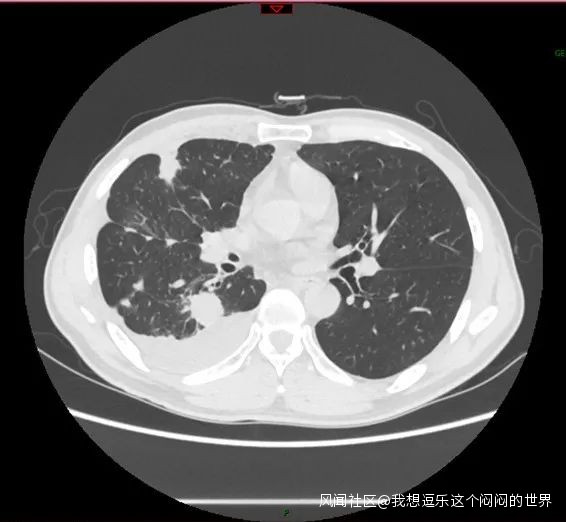

病例1,男,43歲。因“咳嗽咳痰1月餘”在3月份至我院門診就診,行胸部CT檢查發現左下肺巨大佔位。

左下肺佔位,直徑約6cm

這種大小的腫塊基本上考慮是惡性腫瘤,正常流程是要入院明確診斷,然後評估診療方案的。如果淋巴結沒有轉移,或者只有N1(肺門淋巴結)的轉移,是可以考慮直接手術的。

患者在家裏無法就診,同時出現了痰中帶血。直到6月再次就診,複查胸部CT,腫塊明顯增大,並出現了阻塞性肺炎。

左下肺佔位明顯增大,直徑約8cm

同時行PET-CT檢查,發現同側縱隔淋巴結出現了轉移(N2),所幸沒有遠處轉移(M0)。臨牀分期為cT4N2M0,IIIB期,暫時不考慮手術。